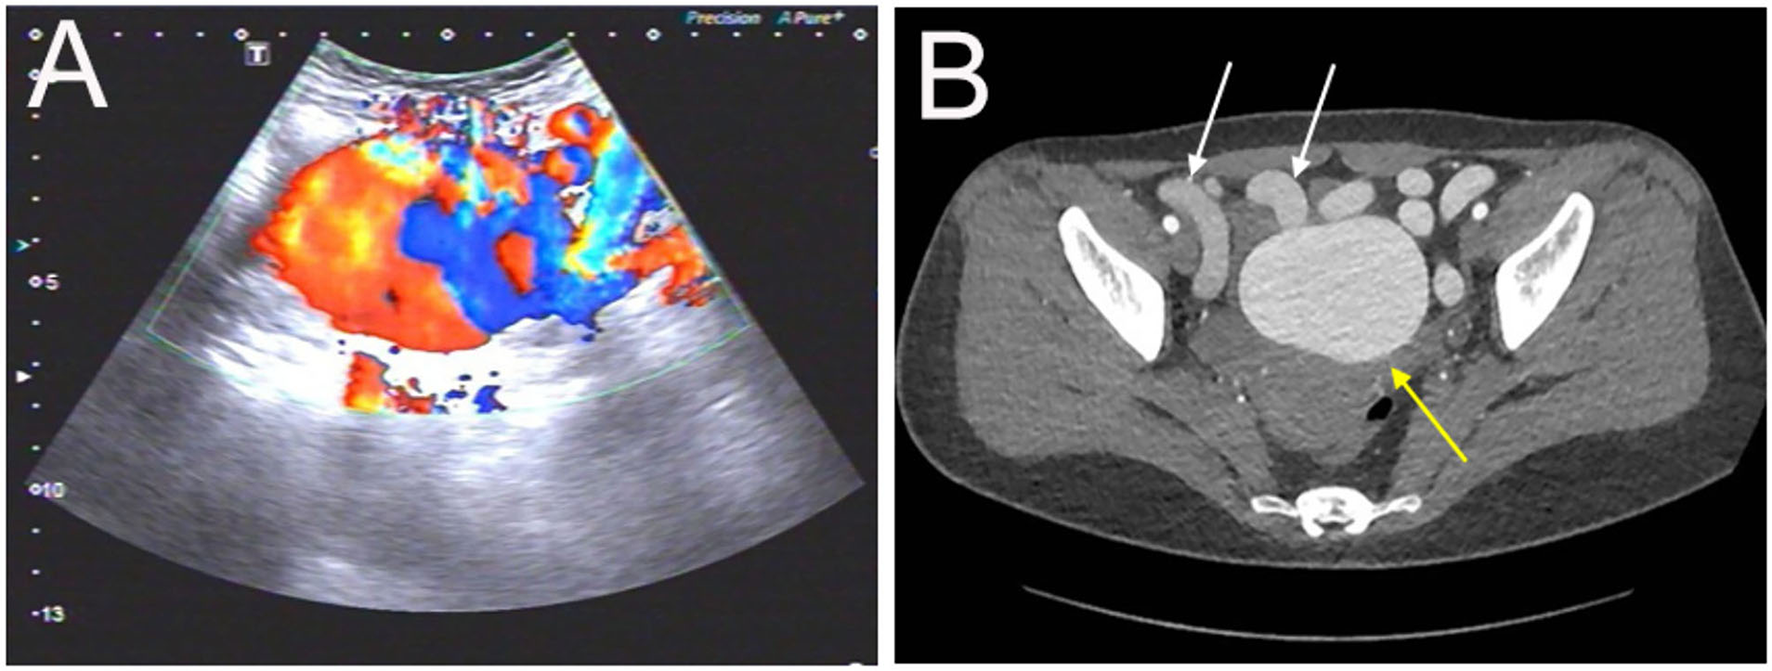

A 32-year-old woman was admitted to our center due to the finding of a pelvic mass with hypervascularity 2 years ago. She was generally asymptomatic and had no related family history. On physical examination, her mass was not palpable, but vascular bruits could be easily auscultated on the abdomen, especially in the peri-umbilicus area. The ultrasound revealed a pelvic mass with an abundant blood flow signal (Figure 1A). CT angiography (CTA) showed the nidus of pelvic arteriovenous malformation (AVM) and aneurysmal-dilated vessel (measured 72 × 56 mm) (Figure 1B). The 3D reconstruction of CTA demonstrated that the AVM had a single feeding artery originating from the splenic artery and two draining veins into the superior mesenteric vein, and then, a portal vein (Figure 2). Digital subtraction angiography (DSA) was used to further evaluate the AVM (Figures 3A–C). It was confirmed that the AVM finally drained into the portal vein and there were no other feeding arteries from bilateral internal iliac arteries (Supplemenatry Video 1). Considering the risk of aneurysm rupture and hemorrhage, the patient was treated with surgical resection of the AVM and ligation of the feeding artery and draining veins (Figure 3D). She recovered well after the operation and was discharged post-operatively on day 6. The 1-month follow-up CTA showed elimination of the abdominopelvic AVM (Figure 4) and the patient was doing well during the following 12 months.

Figure 1

Evaluation of the abdominopelvic arteriovenous malformation (AVM) with color Doppler ultrasound and CT angiography. (A) The ultrasound revealed a pelvic mass with an abundant blood flow signal. (B) The axial view of CT angiography showed the nidus of AVM (yellow arrow) and dilated outflow veins (white arrows) (the aneurysm was measured as 72 ×56 mm).